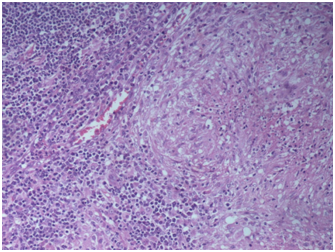

Patient’s complete blood count and peripheral smear was normal. The results of urine culture, blood culture and serology of viruses including EBV, CMV, hepatitis B, C and HIV were negative. Erythrocyte sedimentation rate: 68mm/h, C-reactive protein: 24mg/L (normal<5). HLAB27 was negative and mantaux was 14mm. Blood TB PCR, TB quantiferon Gold test and serology for Brucella was negative. X rays of the spine, pelvis and sacro-iliac joints were normal. Ophthalmological and skin examination was normal. MRI of the Sacro-iliac joint revealed diffuse patchy marrow edema in the bilateral sacro-iliac joints (Figure 1) involving bilateral sacral ala and juxta articular iliac bones and associated with diffuse patchy marrow edema in the vertebral bodies from thoracic to sacrum vertebrae. There was mild reduction of joint space in the bilateral sacro-iliac joint inferiorly with erosive changes in the articular surface of iliac aspect of right sacro-iliacjoint. MRI of whole spine revealed diffuse patchy marrow edema in the vertebral bodies (Figure 2). Bone marrow examination was essentially normal.

Figure 1 MRI of the Sacro-iliac joint revealed diffuse patchy marrow edema in the bilateral sacro-iliac joints.